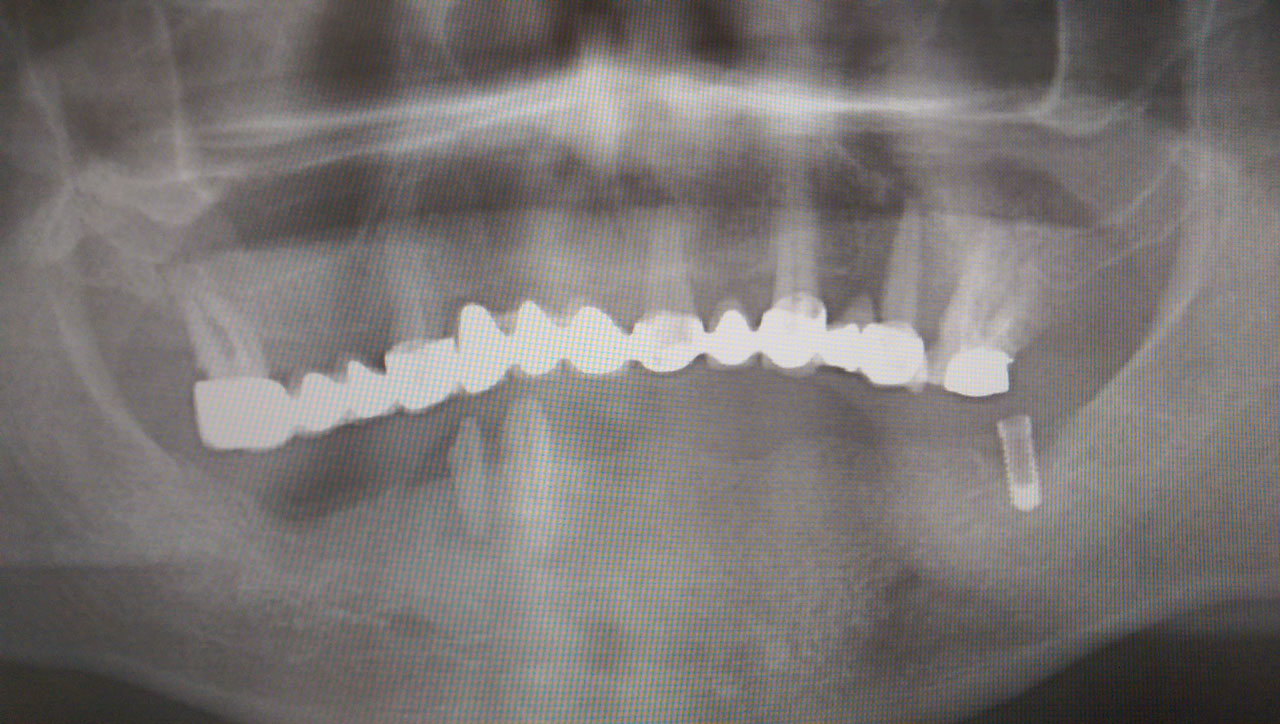

Teljes fogatlanság helyreállítása 2 nap alatt azonnal terhelhető svájci IHDE implantátumokkal és PMMA műanyag hidakkal. Intraorális szkennerrel vettünk lenyomatot az implantáció után, és erre a digitális mintára készítette el a fogtechnika a hidak digitális tervezését, majd faragta ki műanyagból. Ezt a gyors munkát az azonnal terhelhető implantátumok és a digitális lenyomat, tervezés segítségével tudtuk megcsinálni mindössze 2 nap alatt. Dr. Kelemen Péter és a Symbion Fogtechnika munkája.